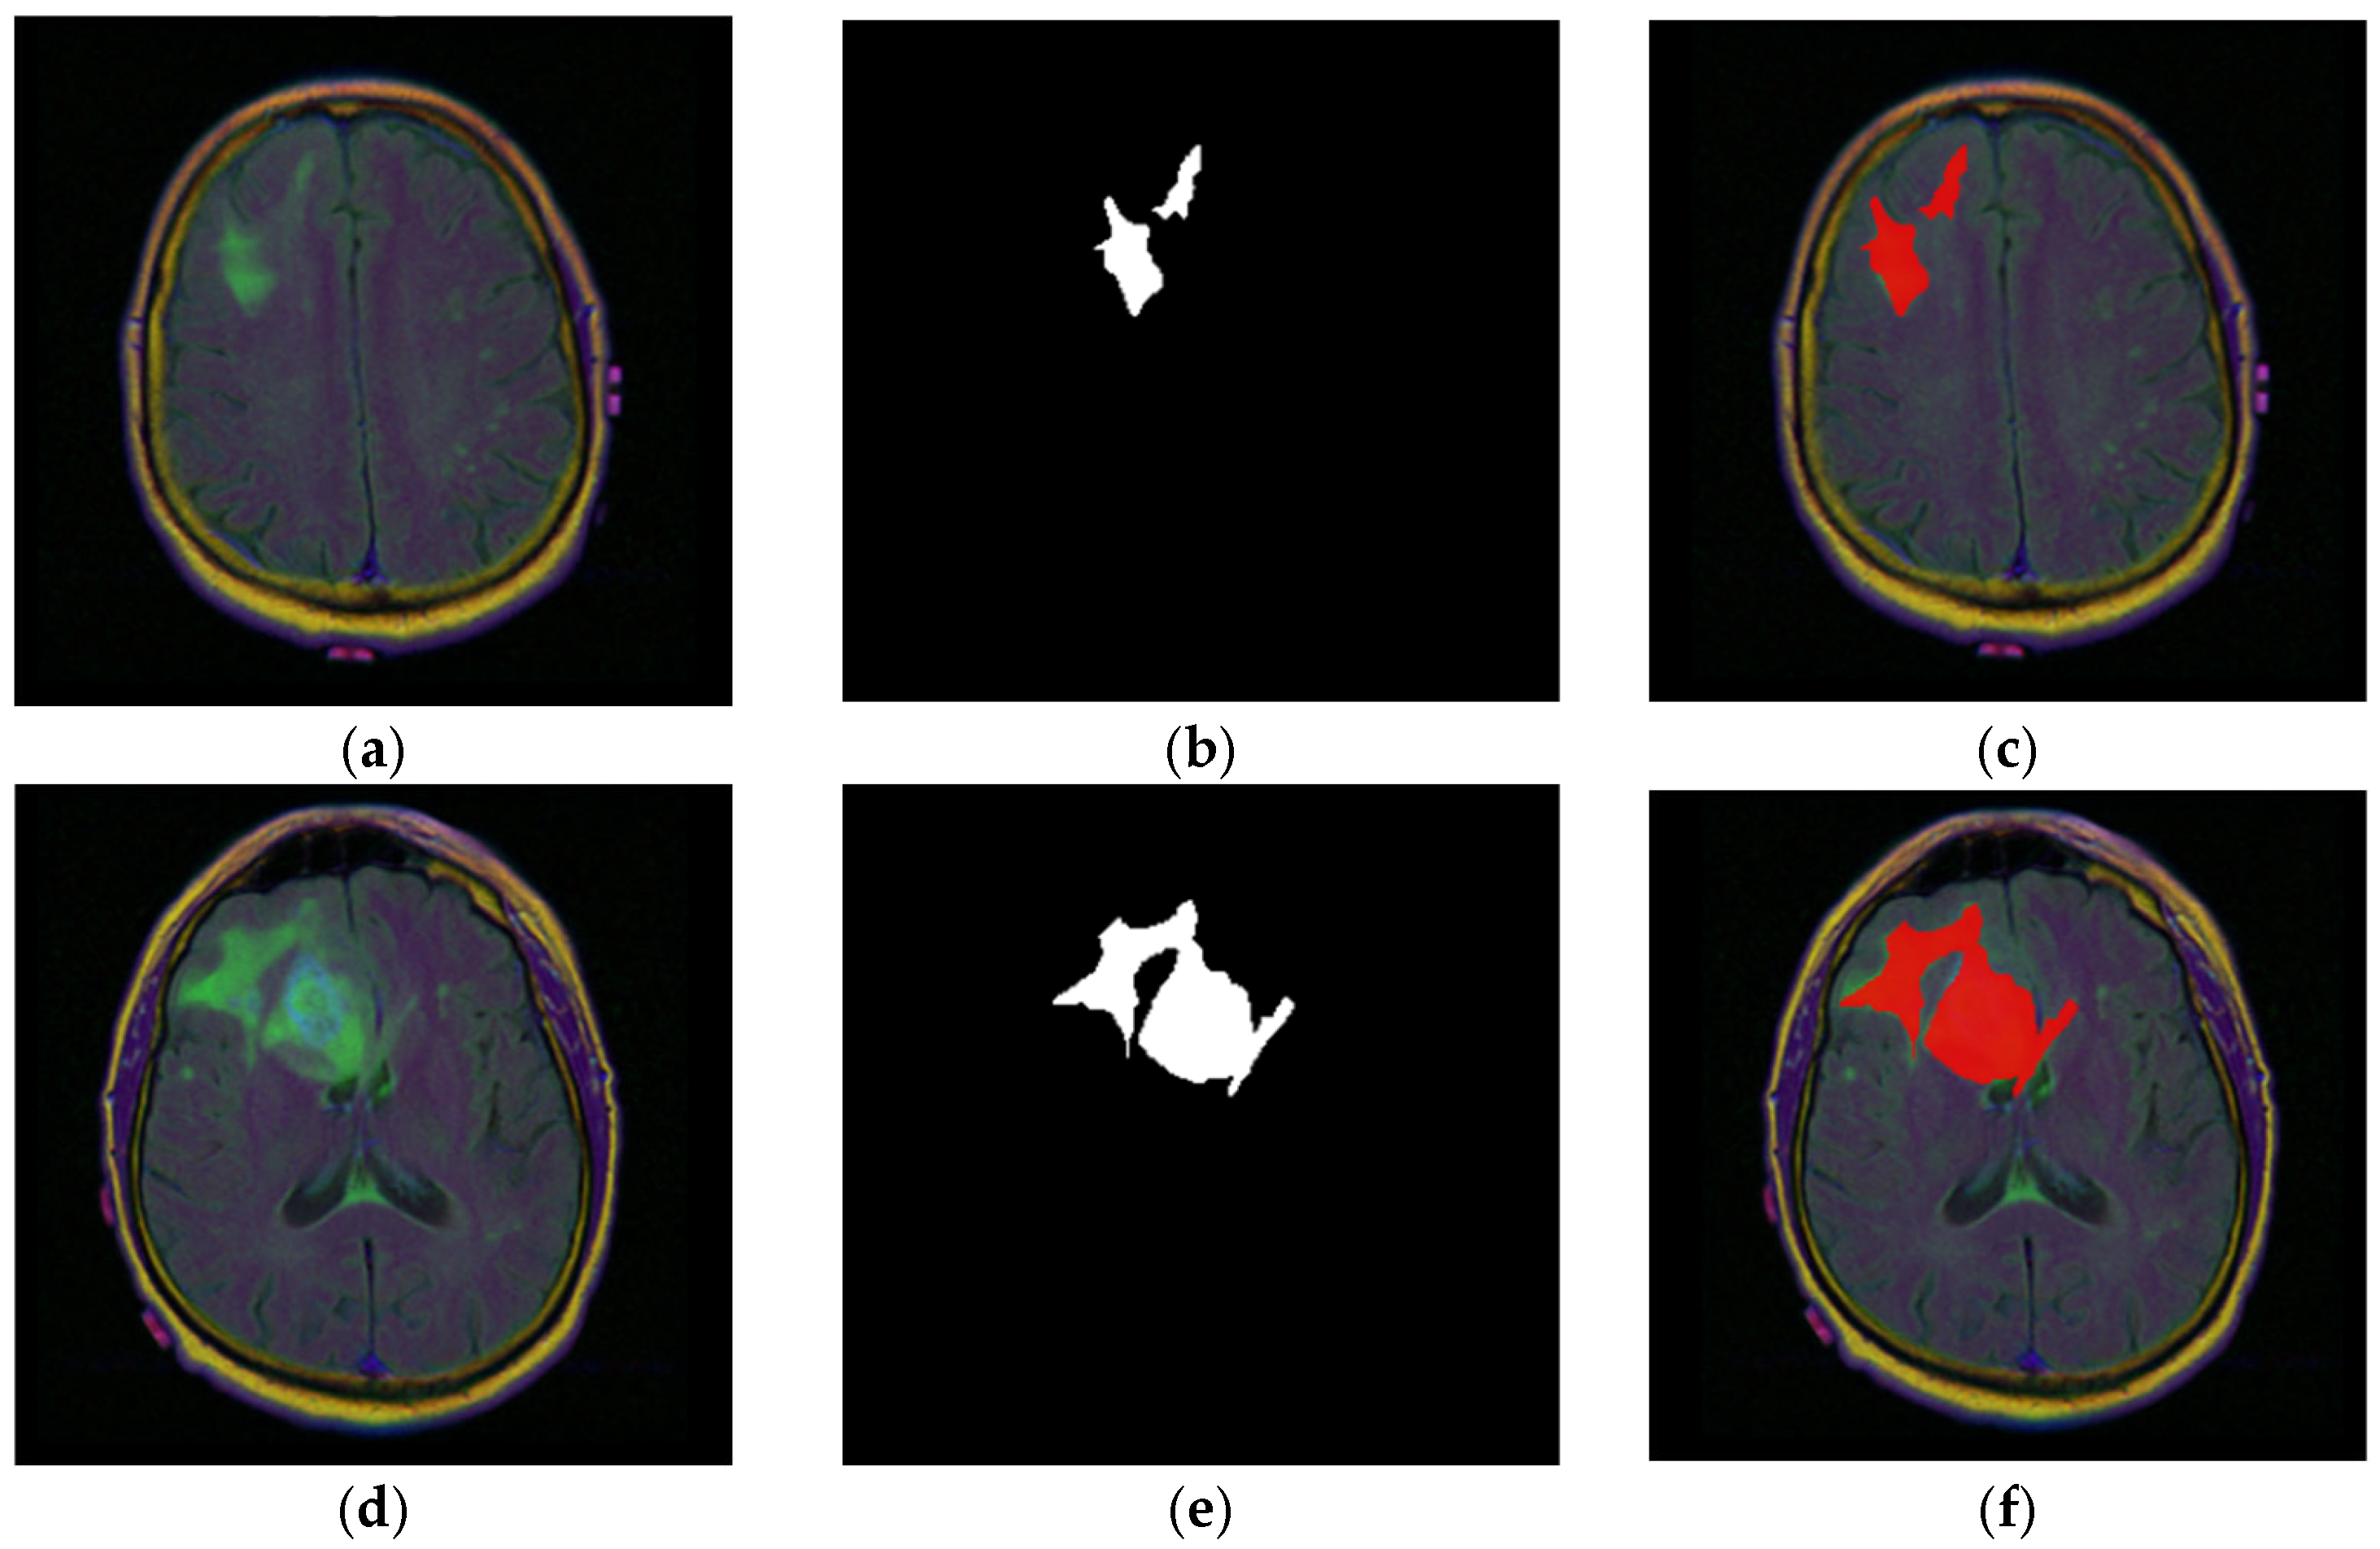

Figure 3a–f zooms in on a single patient, with ID “TCGA_CS_4941_19960909”, to illustrate how expert annotations align with raw images. Figure 3a,d shows two representative FLAIR slices. The corresponding binary masks are displayed in Figure 3b,e, where white pixels mark the tumor footprint. Figure 3c,f overlays mask contours (red) on the original MRIs, highlighting the accuracy of the ground truth masks.

Figure 3.

MRI slice-level examples from patient with ID “TCGA_CS_4941_19960909”. (a,d) Raw FLAIR images; (b,e) ground truth binary expert masks; (c,f) image–mask (red) overlays.

Figure 4a stacks all 23 slices available for the same patient in cranio-caudal order. The sequence reveals how the cranial vault initially appears tumor-free and gradually opens to reveal the lesion, which then enlarges before disappearing again. Figure 4b presents the ground truth masks for those 23 slices without the underlying MRI signal, emphasizing the sparsity of positive pixels in many frames.

Figure 4.

Anatomical order visualization for patient with ID “TCGA_CS_4941_19960909”: (a) Complete set of 23 axial FLAIR slices; (b) ground truth tumor masks.

Figure 5 combines the two views of Figure 4, overlaying every mask on its corresponding MRI slice-image, reinforcing the spatial coherence of the annotations that will later be used as a qualitative benchmark for model outputs.

Figure 5.

Image–mask (red) overlays for all 23 slices for patient with ID “TCGA_CS_4941_19960909”.